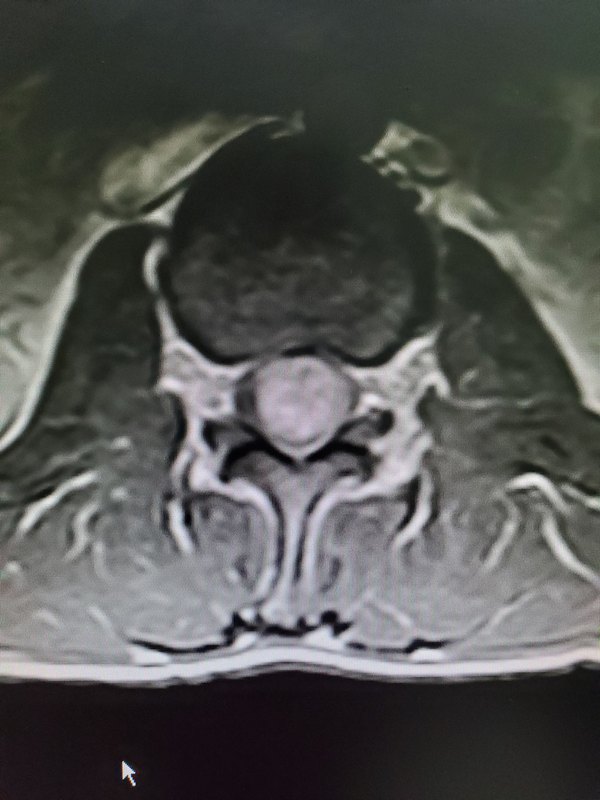

一說到腰痛,我想很多老百姓都有過這種經(jīng)歷,大家普遍都認為,腰痛嘛,無非就是由于腰椎間盤突出、腰肌勞損所致,因此很多人就因為這個“想當然”,而以觀察或者自行買藥處理,從而延誤了治療。 近期,我收治了一位患者就是如此,他以“反復腰背疼痛半年”入院,最近拍了腰椎MR提示“腰2-3椎管內神經(jīng)鞘瘤”,之所以耽誤這么久才發(fā)現(xiàn)病根所在,就是因為想當然的認為,腰痛無非就是腰椎間盤突出或者腰肌勞損所致,隨便買點藥擦一擦就好了,結果耽誤了這么久,實在痛的受不了了才去檢查。這是患者的片子。 這類疾病,也不可怕,多呈良性,首選手術治療,絕大多數(shù)可以全切,術后疼痛解除效果良好。